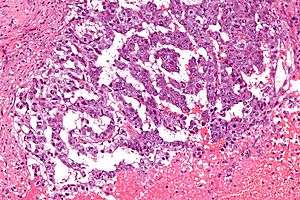

| Micrograph showing the yolk sac component of a mixed germ cell tumour. H&E stain. | |

EST can have a multitude of morphologic patterns including: reticular, endodermal sinus-like, microcystic, papillary, solid, glandular, alveolar, polyvesicular vitelline, enteric and hepatoid.

Schiller-Duval bodies on histology are pathognomonic and seen in the context of the endodermal sinus-like pattern.